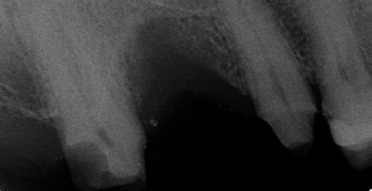

Wenn aufgrund der röntgenologischen Diagnostik klar ist, dass ich pulpennah exkavieren muss, lasse ich Carisolv einwirken und exkaviere dann mit dem PolyBur P1. Ich informiere den Patienten, dass eventuell eine Wurzelbehandlung folgen könnte, ich dies jedoch zu vermeiden versuche. Ist die Karies tatsächlich weit fortgeschritten, also tief im Dentin, kann es natürlich der Fall sein, dass ich mit PolyBur P1 die Pulpa eröffne.